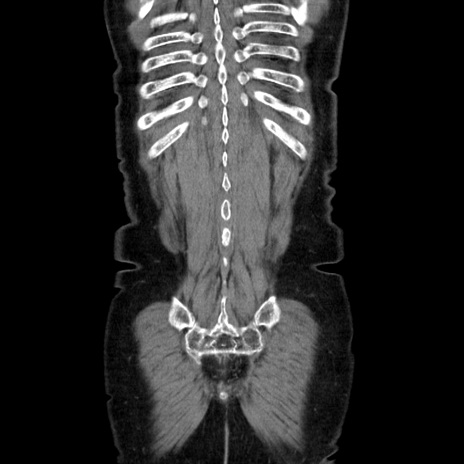

症例5(冠状断像)

【症例】70歳代女性

【主訴】お腹が張る

【現病歴】1週間くらい前から腹部膨満の自覚あり。昨日夜から増悪したため、本日救急外来受診。

【身体所見】意識清明、BT 36.5℃、BP 165/106mmHg、HR 80bpm、SpO2 98%、腹部:膨満、軟、自発痛・圧痛なし、触診にて不快感あり、腸蠕動音:減弱

【データ】WBC 12600、CRP 1.04